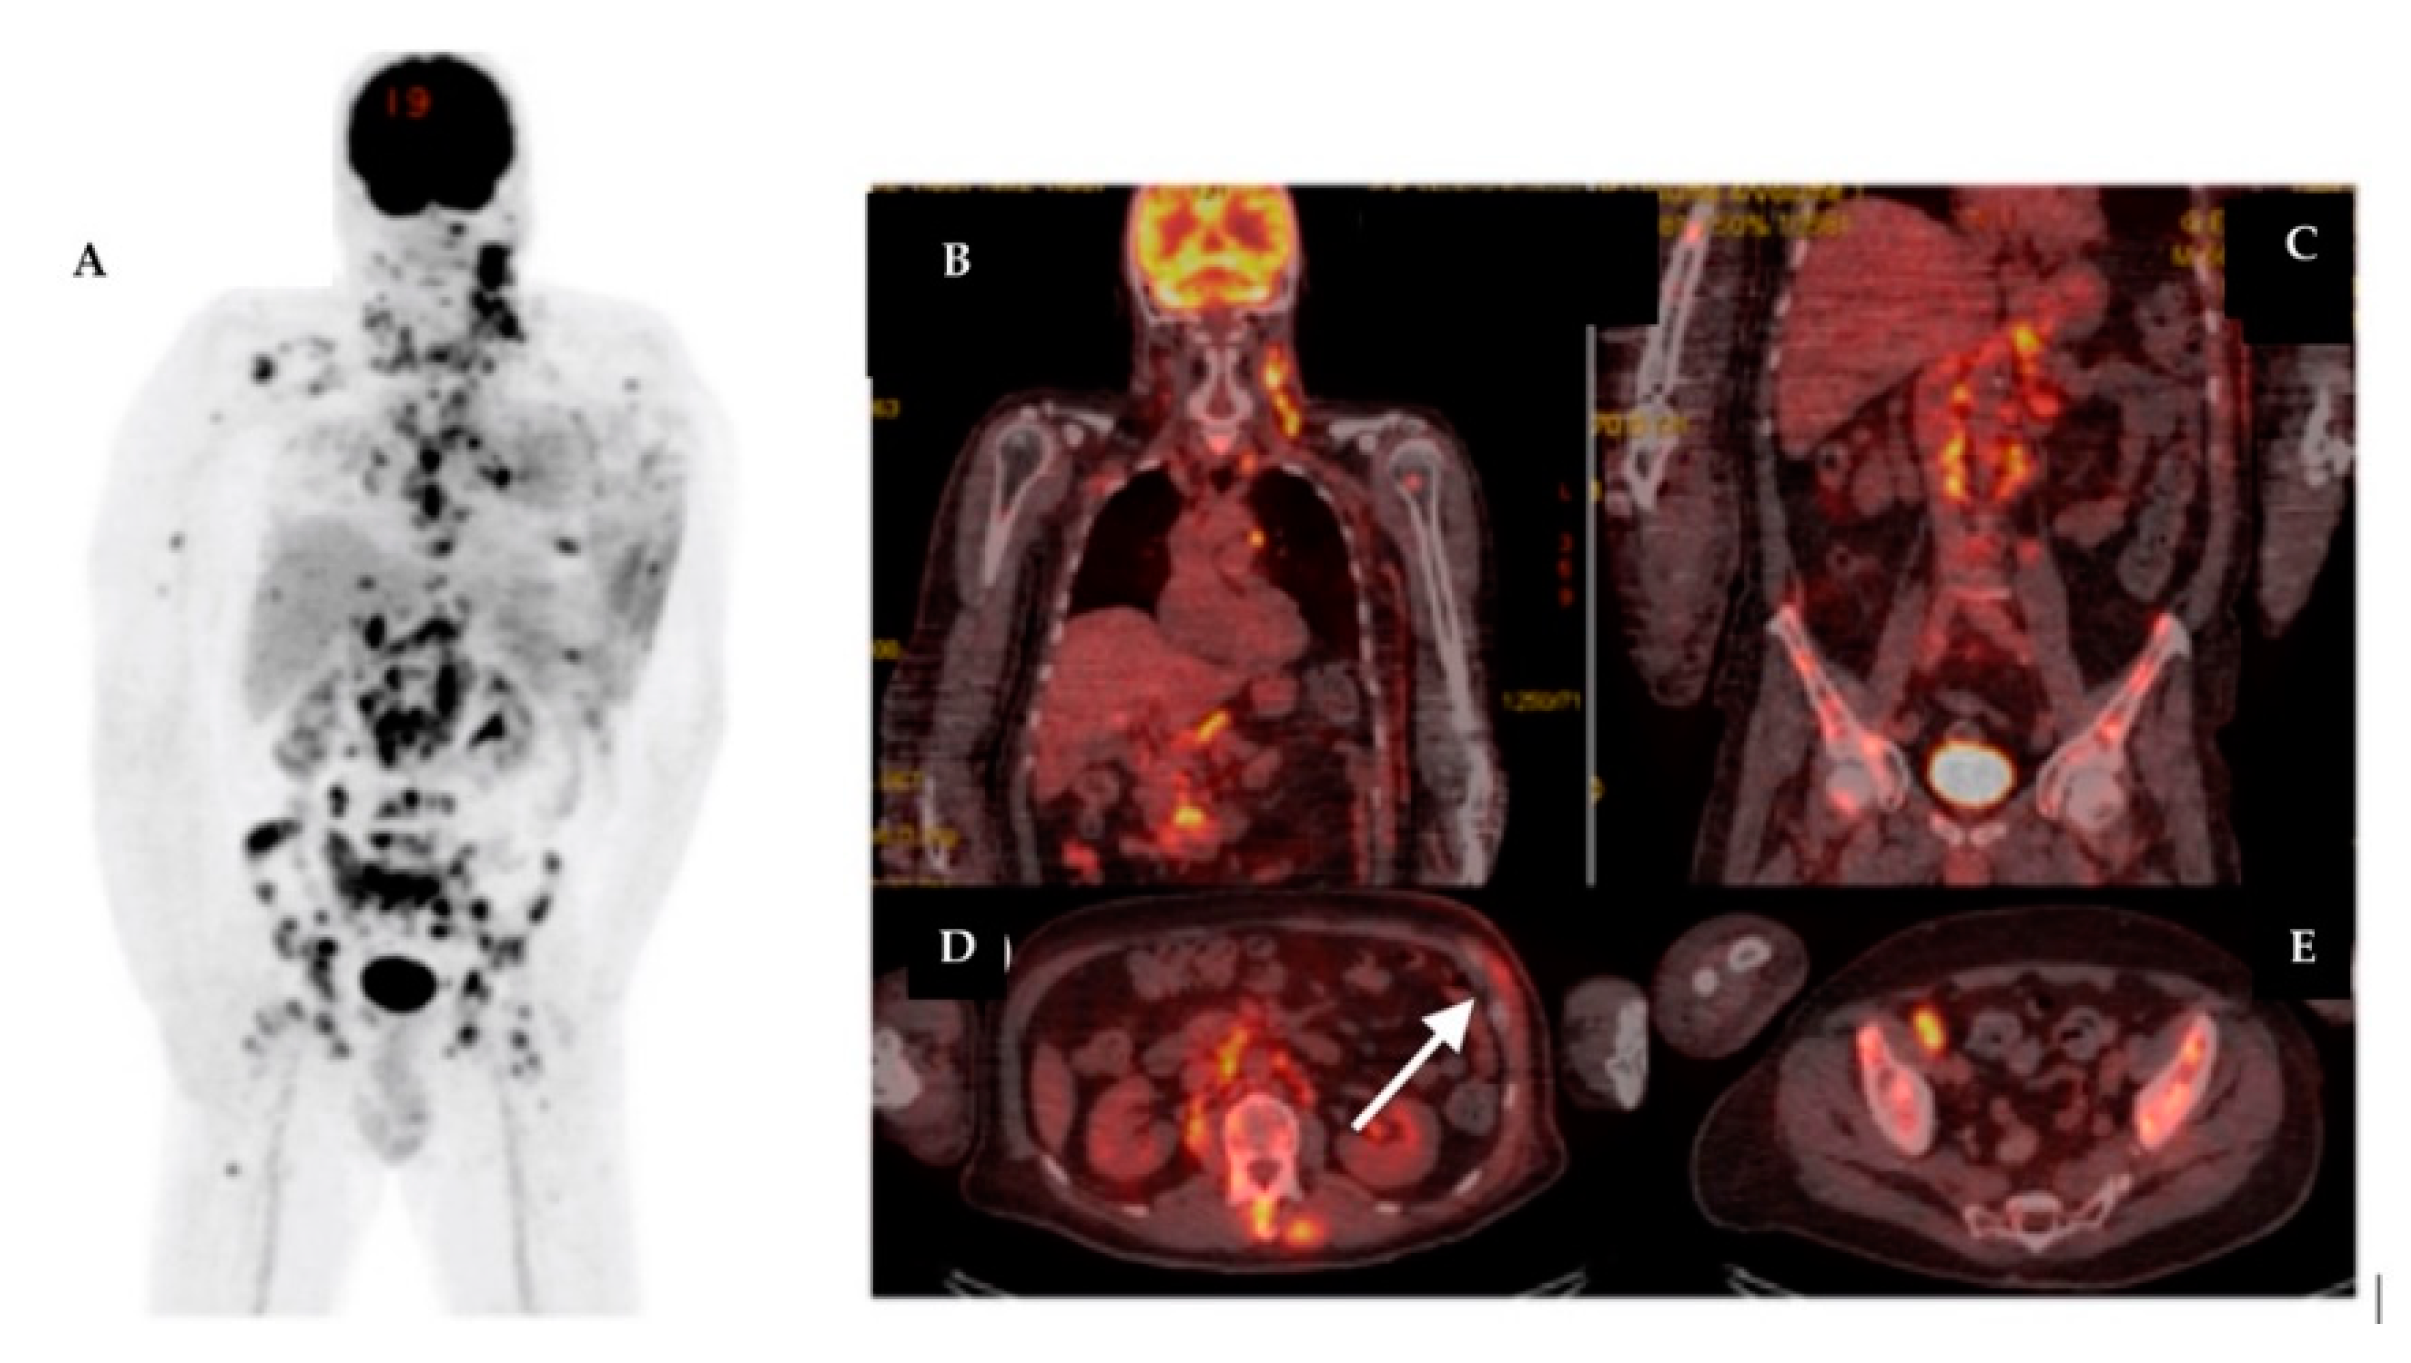

| 19 | 74 | IDC | RM + ALND | Yes | Yes | IIIC | LN, Bn | LN, Sk, M | 6.21 | – | – |

| 20 | 59 | IDC | RM + ALND | Yes | Yes | IIIB | – | LN, Sk | 8.6 | – | – |